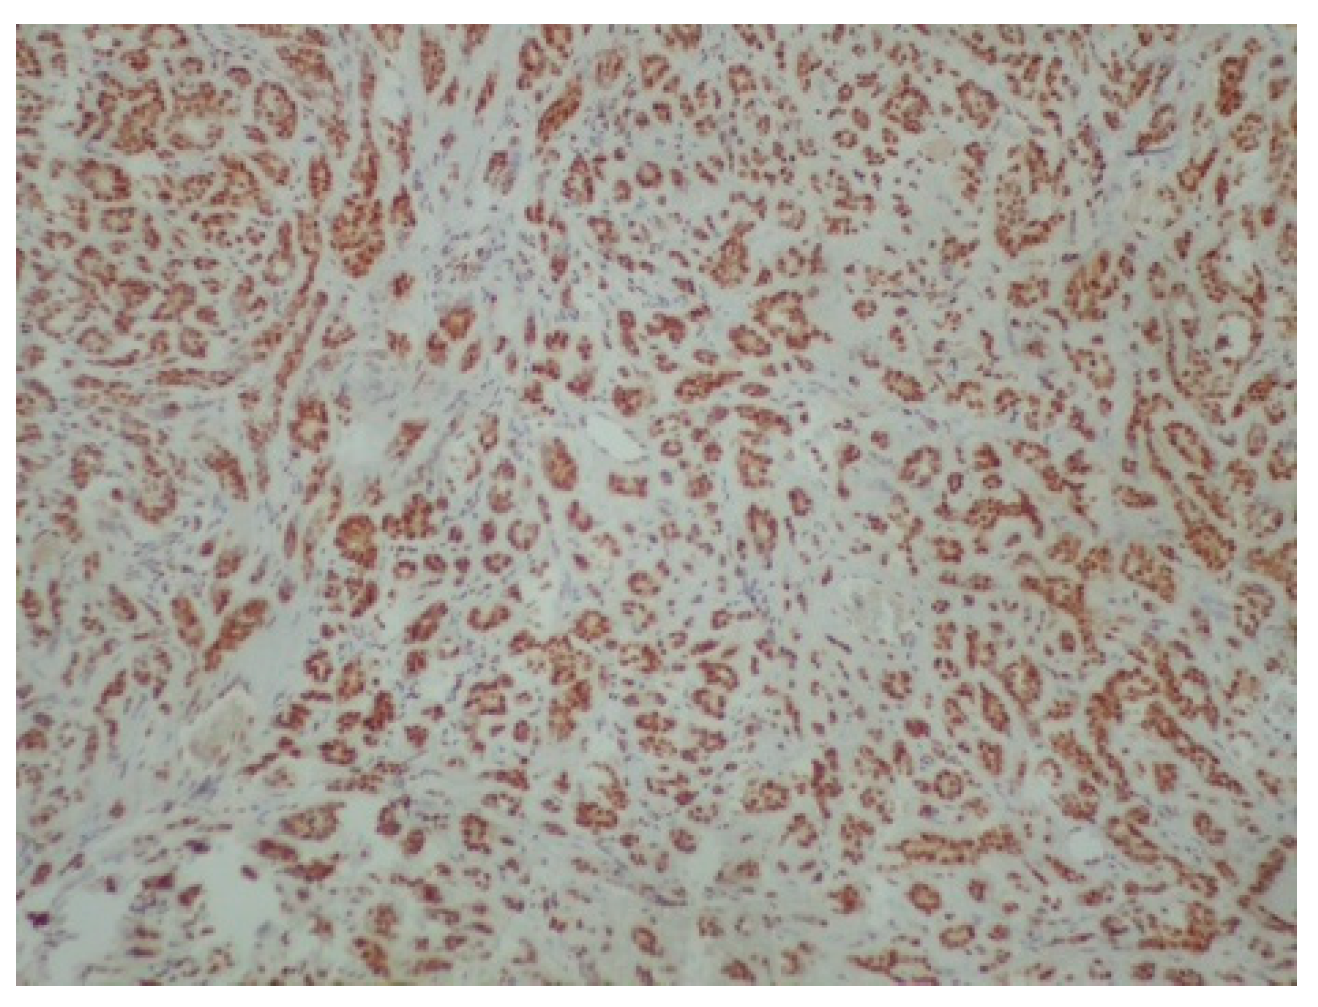

2. Case Presentation

3. Discussion